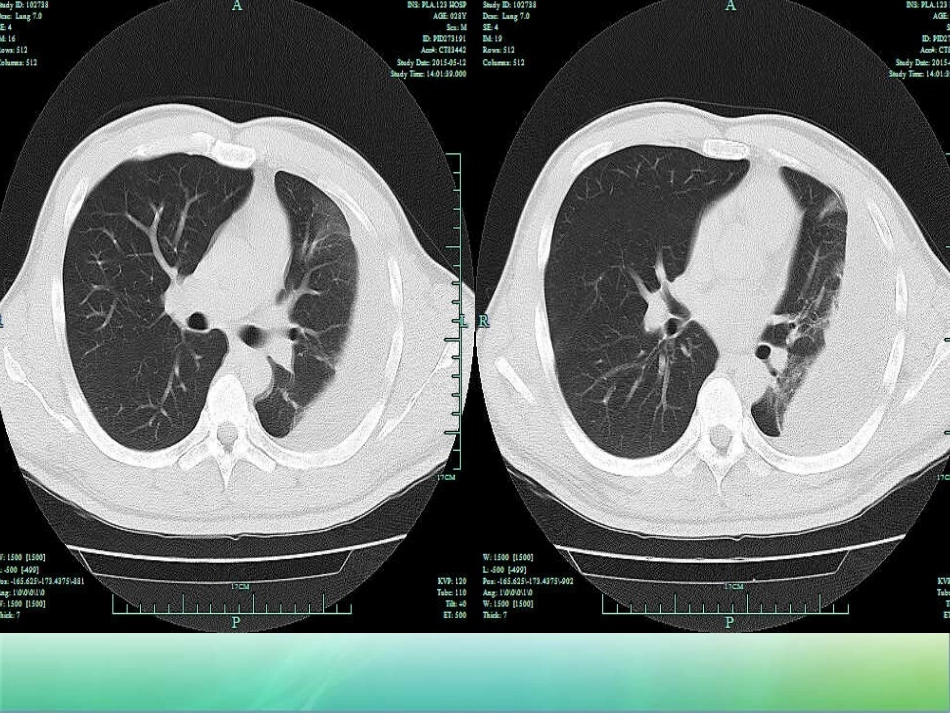

胸膜纤维板剥脱术心胸外科--马达病史介绍•患者王涛,男,27岁,缘于5月前被人用刀刺伤左侧胸背部,当时感胸背部疼痛,伴轻度胸闷,无咳嗽、咳痰,无咳血、呼吸困难,无发热、畏寒,无乏力、盗汗等不适,就诊于当地医院,行胸部CT检查见“左侧胸腔少量积液”,未予进一步治疗。1月后患者感胸闷明显,偶有咳嗽、咳痰,痰中可见陈旧性血块,就诊于淮南市人民医院,复查胸部CT见左侧胸腔积液较前明显增多,予以行左侧胸腔闭式引流术,并予以输液治疗,患者病情好转后出院。5月来患者常感胸闷,平时无咳嗽、咳痰,无心悸、气促,无咯血,无呼吸困难,工作后感胸闷明显并感乏力,休息后乏力好转。4天前患者再次于淮南市人民医院行胸部CT检查示“左侧大量胸腔积液,局部形成包裹性胸腔积液,左肺局限性肺不张”。•入院查体:生命体征平稳,胸廓对称无畸形,左侧胸廓塌陷,呼吸移动度两侧对称,左侧语颤减弱,未触及胸膜摩擦感。左侧叩诊呈实音,右肺叩诊呈清音,胸骨无压痛,胸廓挤压试验(-),胸壁无压痛。听诊左肺呼吸音弱,右肺呼吸音清,未闻及干湿性啰音。心脏及腹部检查未见异常。•辅助检查:2015-05-08淮南市人民医院胸部CT示“左侧大量胸腔积液,局部形成包裹性胸腔积液,左肺局限性肺不张”。•行左侧胸腔闭式引流后引流出暗红色血胸浓稠胸水,但引流后肺部无明显复张。考虑患者5月前外伤后胸腔积液持续渗出,难以吸收,压缩左肺后引起肺不张,局部胸膜表面纤维化,需要进一步手术治疗。手术及术后•积极完善相关检查,2015-05-14在全麻下行左侧开胸探查+胸膜纤维板剥脱术。术中探查壁层胸膜及左下肺脏层胸膜表面纤维化形成较厚纤维层,厚约0.5cm,质韧,与周围组织界限尚清晰,粘连较紧密,融合包围成腔。切开胸膜外层,吸出暗红色血胸胸水约800ml,其中可见白色絮状物。予以逐层切除、分离。术后胸引管接负压吸引;予以止血、抗感染、促进排痰等对症治疗,嘱患者咳嗽、排痰,锻炼肺功能,促及肺复张,观察引流管情况避免堵塞。恢复•患者术后恢复情况可,术后早期偶有痰中带血,为陈旧性血丝,无胸闷、气促等不适,术后多次复查肺部复张术前好转,好转后出院。概述•胸膜剥除术是剥除胸膜壁层及脏层增厚的纤维层(板),达到既消除胸膜腔内的病变组织,又使肺组织解脱纤维板的束缚而复张的一种手术。此手术不仅使肺功能得到了最大的恢复,而且保持胸廓正常形态,是治疗慢性脓胸的理想术式。适应证•胸膜炎治疗半年以上,已成为慢性脓胸;慢性脓胸已经得到基本控制,每天脓液量在50ml以内,但脓腔依然存在,脓液持续不断;肺内无广泛病变,无纤维化改变,无空洞,无支气管扩张及狭窄,无大的支气管胸膜瘘的慢性脓胸均可行胸膜纤维板剥脱术。•胸膜剥除术适用于:•1.慢性脓胸肺内无病灶,无广泛的肺纤维性变,剥除脏层纤维板后,估计肺组织能扩张者。•2.慢性脓胸无结核性支气管炎、支气管狭窄、支气管扩张和支气管胸膜瘘者。•3.机化性和凝固性血胸。•4.特发性胸膜纤维化。禁忌证•1.结核性脓胸并有活动性肺结核或伴有支气管胸膜瘘者一般不宜此手术。•2.患者身体虚弱,全身情况差,不能承受手术创伤者。准备•应做痰和胸液检查,以发现致病菌和恶性肿瘤细胞。•痰液中应无抗酸杆菌,痰和胸液中应无恶性肿瘤细胞。•胸部平片检查,对侧肺内应无活动性结核病灶。断层胸片、CT扫描或MRI检查可显示患侧有无空洞及其他肺内病变。•纤维支气管镜检查对排除支气管内病变十分重要,必要时做支气管碘油造影。结核性脓胸术前应行抗结核治疗2~4周以上,血沉接近正常。•术前应根据病情输血、输血浆、加强营养,纠正贫血、凝血机制障碍和水电解质失衡。全身和局部应用有效的抗生素控制感染,冲洗脓腔。•如果术前估计术中失血多,术前应多备血。麻醉和体位•最常用的麻醉方法是静脉复合麻醉。低温麻醉和术中控制性低血压可减少失血量。•侧卧位,常用后外侧切口。具体方法•1.经第5或第6肋骨床入胸,上下兼顾,便于胸顶和后肋膈角同时解剖分离•2.切除肋骨,切开骨膜,进入胸膜外层,用弯剪刀或手指做钝性分离。胸膜外剥离至能插入肋骨牵开器为止。增厚的壁层胸膜表面常有肋骨压迹。...